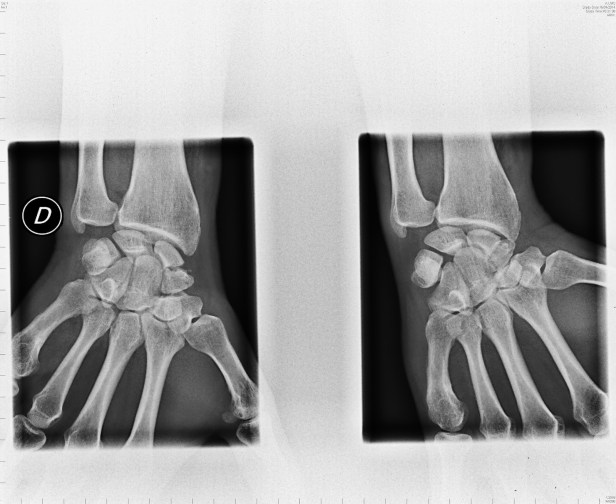

En las siguientes Radiografías vemos lesiones traumáticas de hueso escafoides: la primera es de un paciente de Urgencias, y la segunda es de un paciente con Fractura no consolidada.

Protocolo de rayos x estandarizada con vistas de muñecas extendidas incluyendo la parte distal del radio y las partes proximales de los metacarpianos. Es una serie de cuatro imágenes.

1º.- Vista posterior-anterior estándar con la muñeca en desviación cubital.

2º.- Vista lateral (o de perfil) del carpo y radio / cúbito distal.

3º y 4º.- Vistas oblícuas: una con la mano en el 45 ° de supinación y el otro con 45 ° de pronación.